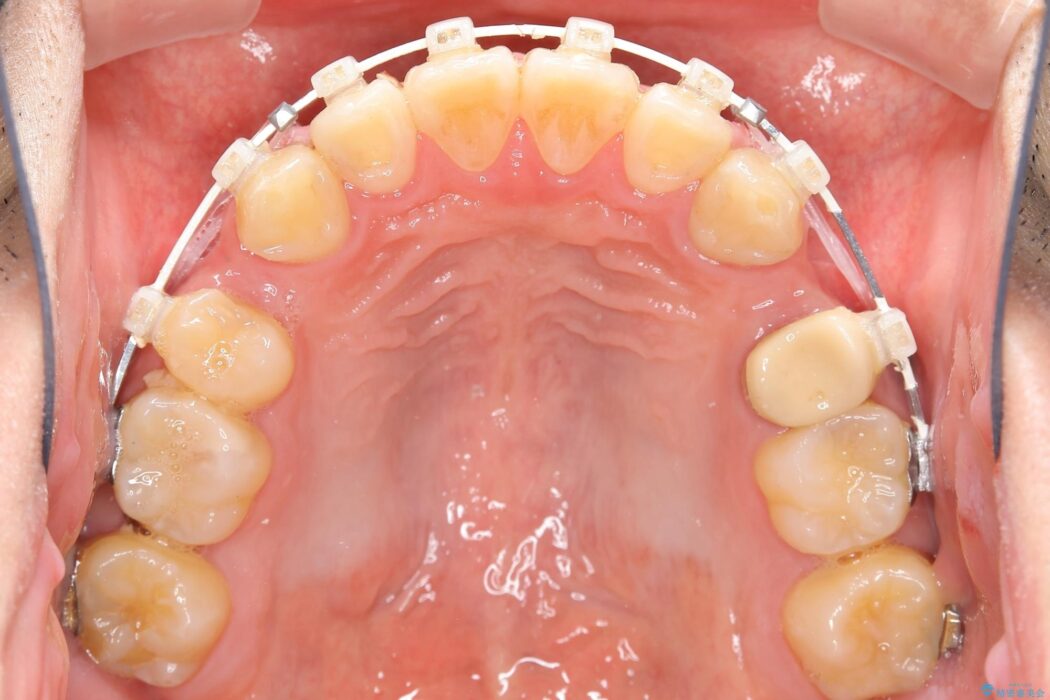

上の歯の出っ歯と下の歯のガタつきが気になるとご来院された患者様です。

出っ歯とガタつきの改善には抜歯が必要と診断し、上下左右第一小臼歯を抜歯することとしました。

抜歯でスペースができるため、歯の移動量が多いことから表側ワイヤー矯正装置で治療を行いました。